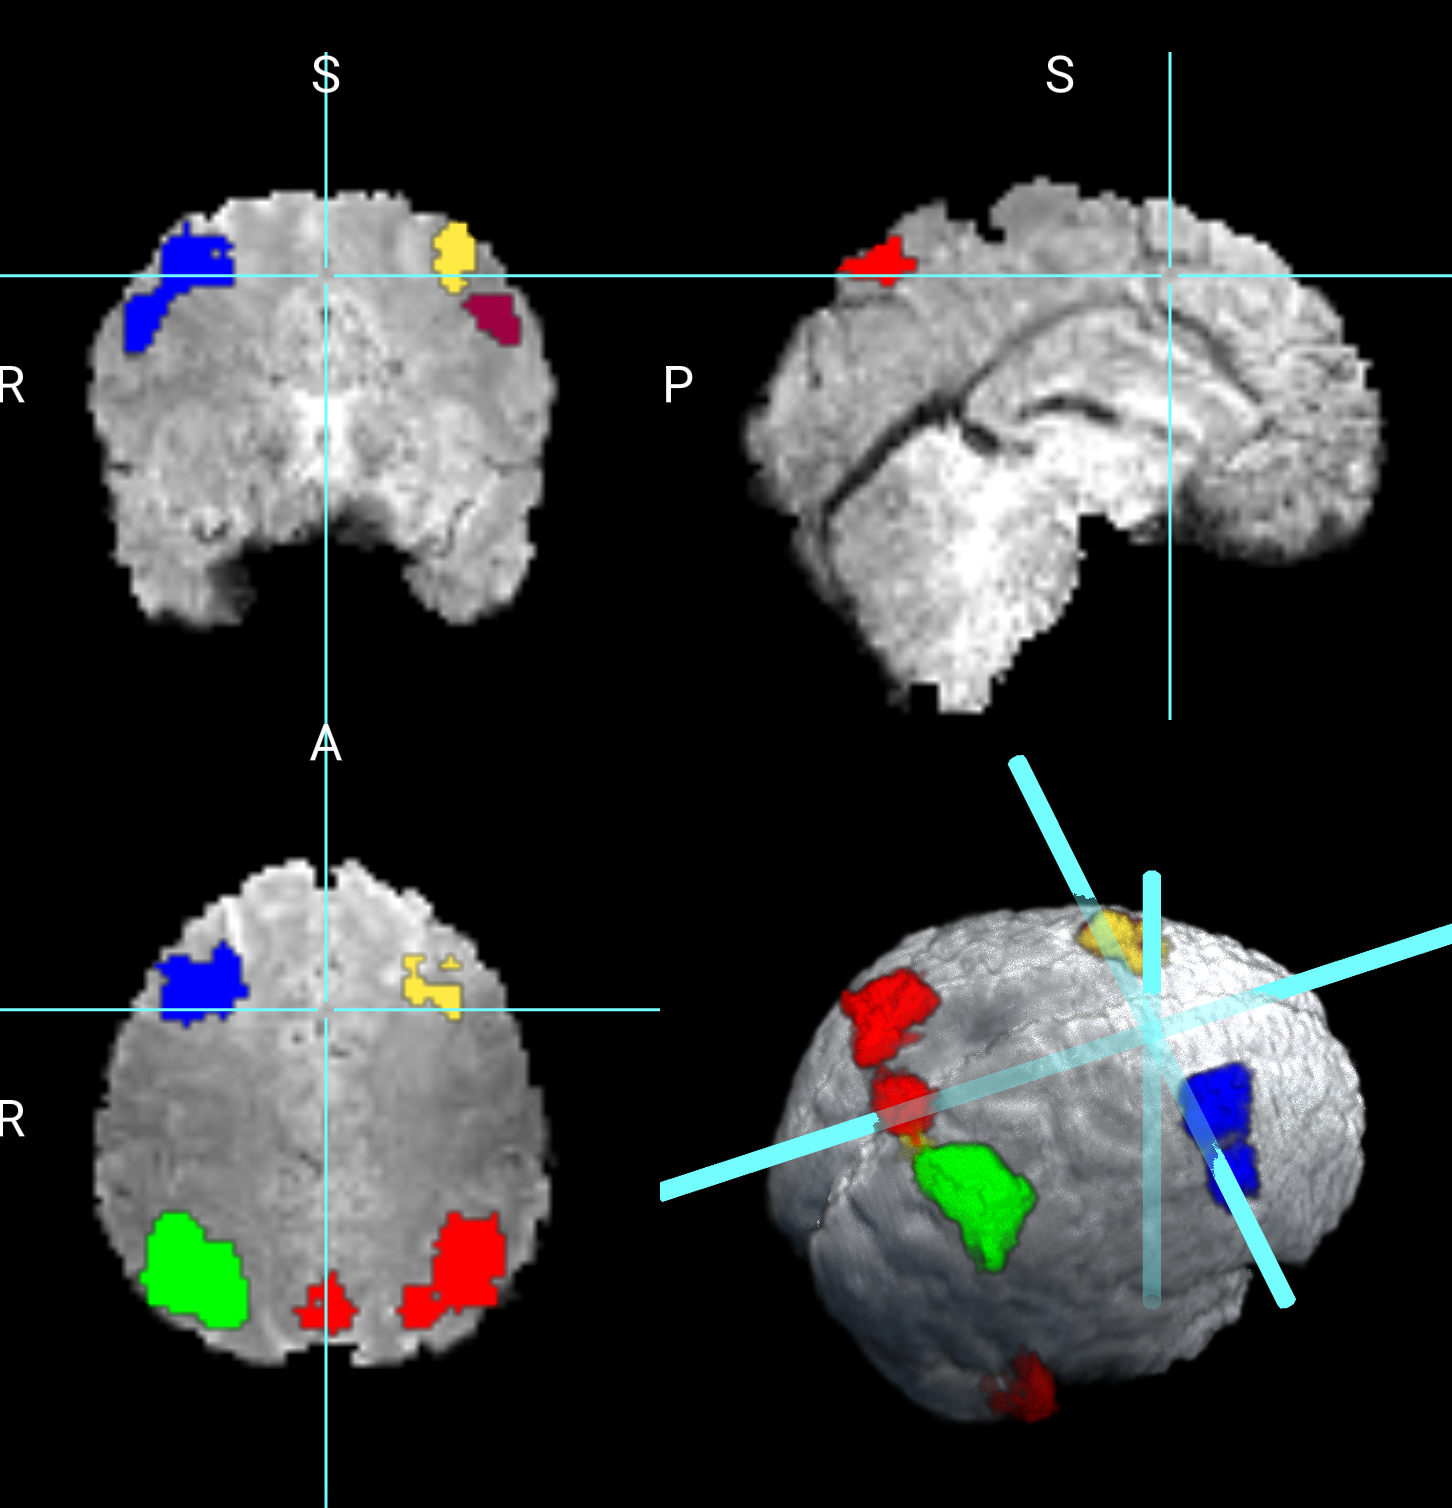

We consider two maps of coefficients, the first is the intercept, which is the average activation for the contrast 2 back versus 0 back of the Working Memory task. The second is the map associated with the variable sex. We did not find any significant differences in the working memory contrast between females and males. Figure 3 shows the results for the intercept revealing 4445 active voxels. The larger cluster in red shows 1268 voxels encompassing 24 distinct brain regions as subdivided by the Tailarach Atlas, (labels can be found here http://www.talairach.org/about.html#Labels). Within this cluster, larger active regions are in the right parietal lobe, including inferior, superior, precuneous parietal regions. The cluster in green is formed by 1182 voxels, with active regions on the left parietal lobe, including the inferior, superior, precuneous, and cuneous regions. The parietal lobe has been previously identified as playing a key role in working memory [3, 11, 9].

The next cluster in blue shows the right frontal lobe, including the superior and middle frontal gyrus. The cluster in yellow shows 345 voxels in the right frontal lobe, including the superior and middle frontal gyrus. The cluster in light orange shows 276 voxels on the left frontal lobe in the middle frontal gyrus. These regions have also been identified as playing a critical role in working memory [22]. The cluster in burgundy indicates 313 voxels on the right cerebellum at the posterior lobe region. A smaller cluster of 139 voxels was also identified on the posterior lobe at the left cerebellum. The authors in [5] found that the cerebellum can influence the accurate maintenance of working memory.

Refer to caption

Figure 3: Working Memory contrast of 2back versus 0back.